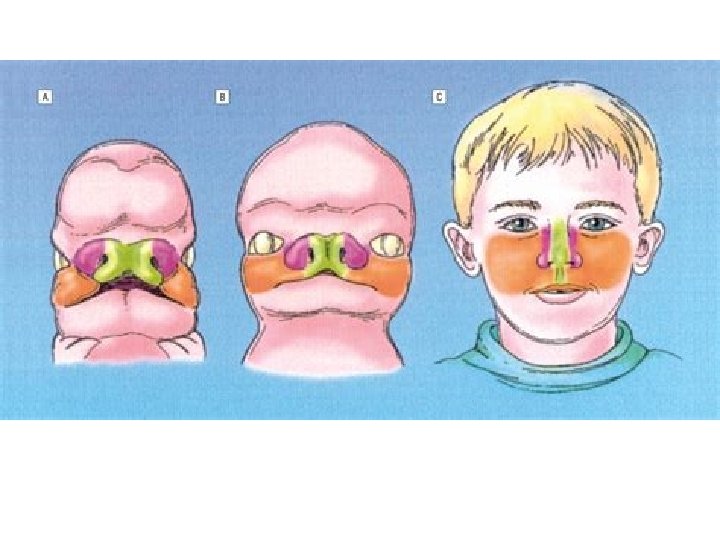

EMBRYOLOGY • Nose develops from frontonasal process which grows between primitive forebrain and the stomodaeum. • Frontonasal process gets divided into median nasal process and two lateral process.

• Olfactory placodes on the frontonasal process become depressed to form olfactory pits which later form nasal cavity.

• Primitive nasal cavities are closed at their posterior ends by bucconasal membrane which ruptures and forms choanae. • Clinical significance: choanal atresia